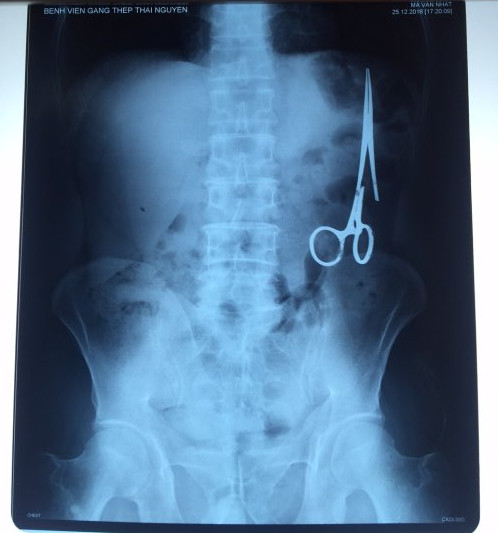

遺留在病人腹中的剪刀

據(jù)越南青年報1月2日報道,在越南首都河內(nèi)醫(yī)療專家的幫助下,越南東北部的太原?。═hai Nguyen)鑄鋼醫(yī)院的醫(yī)生日前從54歲患者M(jìn).V.N腹中取出一把醫(yī)用剪刀。這把剪刀是此前曾為M.V.N手術(shù)的醫(yī)生遺留的,已經(jīng)在其腹中待了18年時間。

醫(yī)務(wù)人員表示,這把剪刀遺留在病人腹部左側(cè),與結(jié)腸緊挨著。剪刀的把手已經(jīng)生銹,部分器官也已經(jīng)與剪刀粘連起來。但在過去多年中,M.V.N沒有任何不適感覺,也從未因為留在腹中的剪刀引發(fā)的相關(guān)問題去看過醫(yī)生。直到2016年12月,M.V.N因為遭遇了一場車禍,才到鑄鋼醫(yī)院進(jìn)行身體檢查。

超聲波檢查顯示,M.V.N的腸子中有個奇怪物體,看起來就像醫(yī)用剪刀。M.V.N證實,他曾于1998年6月份在北江省綜合醫(yī)院接受手術(shù),在此后也從未進(jìn)行過任何手術(shù)。近來,他感到腹部有些疼痛,并試圖通過服用藥物治療。12月27日,M.V.N回到北江省綜合醫(yī)院再次進(jìn)行超聲波檢查,顯示其腹部的確存在怪異物體。